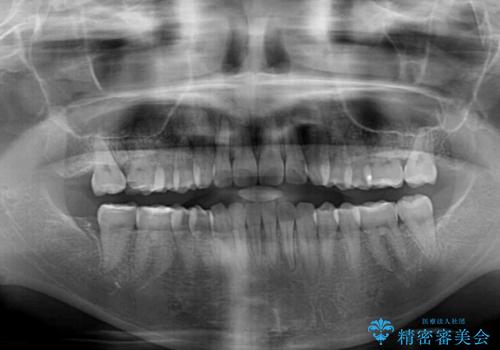

- 1年10ヶ月

下顎が左側にずれているため、裏側矯正ということもあり咬み合わせを整えるのに時間がかかってしまいました。